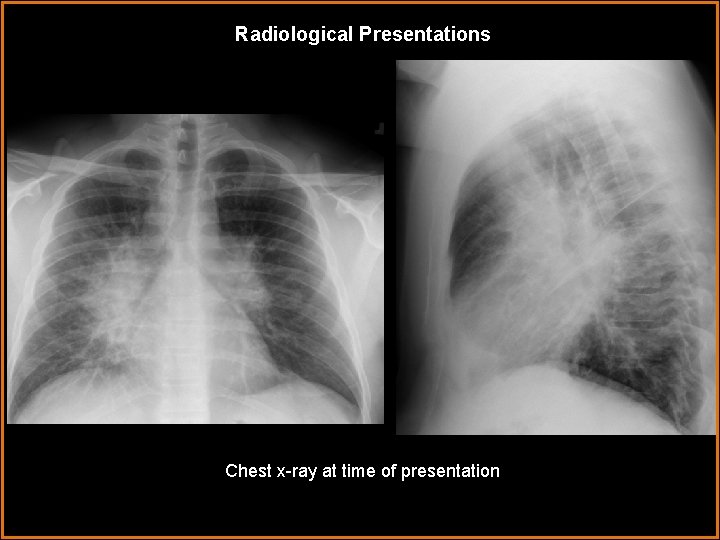

Radiological Presentations Chest x-ray at time of presentation

Findings and Differentials Findings: Chest x ray demonstrates development of new bilateral hilar masses and scattered small nodules in both lungs. CT Chest demonstrates multiple small nodules in a perilymphatic distribution with upper lobe predilection. Multifocal patchy ground glass airspace opacities involving mid and upper lungs. Bronchovascular interstitial thickening. Bilateral symmetric hilar and mediastinal adenopathy. Differentials: • Sarcoidosis • Lymphangitic spread of tumor with malignant lymphadenopathy